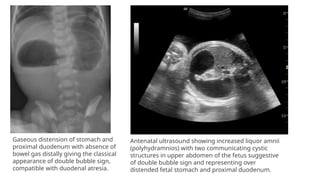

Gaseous distension of stomach and

proximal duodenum with absence of

bowel gas distally giving the classical

appearance of double bubble sign,

compatible with duodenal atresia.

Antenatal ultrasound showing increased liquor amnii

(polyhydramnios) with two communicating cystic

structures in upper abdomen of the fetus suggestive

of double bubble sign and representing over

distended fetal stomach and proximal duodenum.